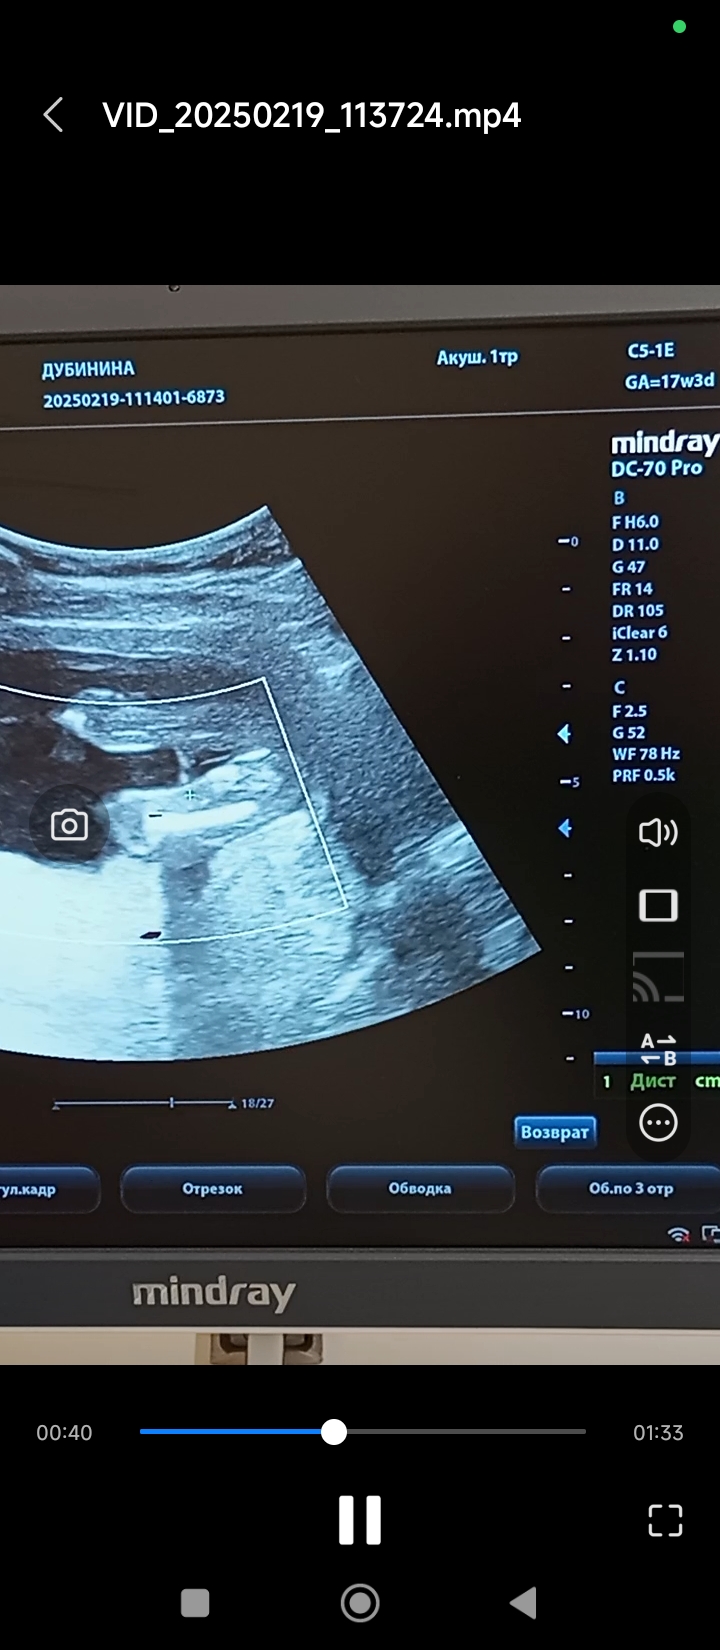

Валентина в Благополучная беременность 9 месяцев Кто тут? Мальчик или девочка? Пол малыша Кто тут? Посмотрите еще 20 записей на эту тему Лучший ответ Мама Лиля Вы уже раз 6 это фото выкладываете, вам пишут, что девочка, вы что хотите еще услышать? 28.02.2025 Ответить Мама Стифлера Мама Лиля, хочет услышать, что пиписька отросла судя по всему 28.02.2025 Ответить Ольга Галка, 😂😂😂 28.02.2025 Ответить Светлана Галка, может, к завтрашнему дню вырастет 28.02.2025 Ответить Отменить Ответить Анастасия Конечно, дочка ) 28.02.2025 Ответить Ornella Mutit Девочка💗 28.02.2025 Ответить Кошка В Сапожках Девочка 100% 28.02.2025 Ответить Виктория Девочка 28.02.2025 Ответить Дашик Девочка. Мне кажется мальчиков сразу видно. 28.02.2025 Ответить Eva Девочка тут явная) Ничего не торчит 01.03.2025 Ответить Ольга У вас мальчик 100%! Без сомнений! 😂 28.02.2025 Ответить Пол малыша Пол по узи Чаты Беременных Выберите чат: Январята-2026 Февралята-2026 Мартята-2026 Апрелята-2026 Майчата-2026 Июнята-2026 Июлята-2026 Августята-2026